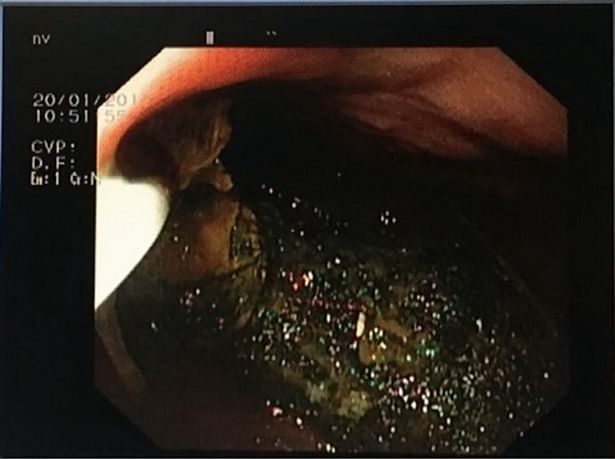

仔细一看,原来那是巨大的毛球!

由于巨大毛球占据胃部80%,塞住少女消化系统,医生必须开刀取出。

最后,医生从胃部切开,取出毛球,一量竟然有足足2公斤重。然而,少女父母也不清楚这团毛球到底如何形成。